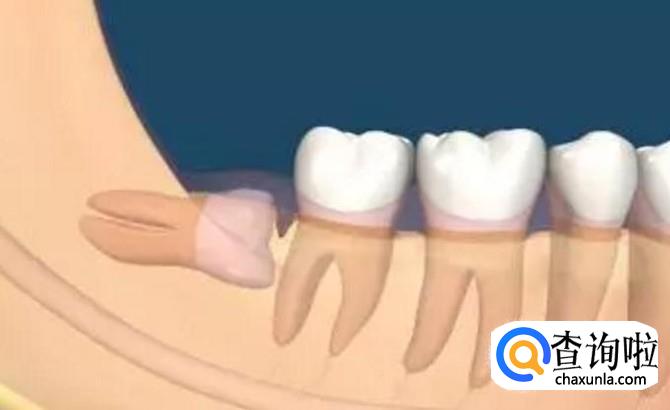

最后,我们需要根据实际情况来确定是否需要拔掉智齿,如果智齿直接顶到另一颗牙齿生长的话,这样的智齿我们也是需要拔除的,不然我们的整体牙齿都会有一定的伤害,这是必须要拔的。